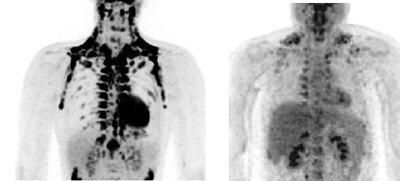

El interés aumentó al encontrar este tejido en embriones humanos y recién nacidos, donde es relativamente abundante. Y despegó definitivamente en 2009 con la publicación de tres trabajos de otros tantos equipos distintos en The New England Journal of Medicine en los que se describió su presencia y actividad en adultos. A ello contribuyó notablemente el PET-TAC, un escáner de diagnóstico por imagen muy útil en la detección de tumores.

Esta tecnología se basa en la combinación de dos técnicas. El PET (tomografía por emisión de positrones) que identifica alteraciones metabólicas, como el elevado consumo de energía y proliferación celular que se relaciona con el desarrollo de células cancerígenas, con el TAC (tomografía axial computerizada), una especie de rayos X mejorados y más precisos. "Algunos oncólogos se dieron cuenta de que personas sanas daban falsos positivos de cáncer en estudios de PET-TAC", recuerda Francesc Villarroya, catedrático de Bioquímica y Biología Molecular de la Universidad de Barcelona.

Uno de los tres equipos que hace dos años confirmaron la existencia en adultos de grasa parda estaba formado por investigadores finlandeses y suecos que recurrieron al PET-TAC. Compararon la reacción de cinco pacientes en un ambiente templado y otro frío. Tras salir de este último, pudieron identificar con claridad el nuevo tejido graso en estas personas. Una biopsia confirmó que se trataba de grasa parda.